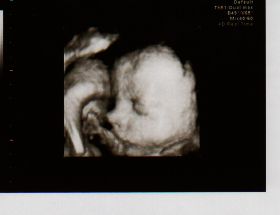

13.10.2008- další UTZ, dostali jsme těhotenskou průkazku, máme první foto z UTZ

22.12.2008- velký UTZ v Centru Prenatální Diagnostiky na Veveří, vše je v pořádku, poprvé se mnou byl i manžel. Čekáme HOLČIČKU.